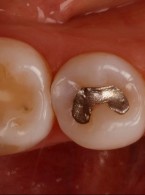

Leczenie endodontyczne drugiego zęba trzonowego szczęki z pojedynczym korzeniem i pojedynczym kanałem korzeniowym

Zobacz więcej